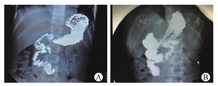

19例于术后1个月内症状明显缓解,但随后随访中发现部分患儿症状反复。术后3个月、6个月、1年和2年因腹痛或呕吐等症状复发再次入院的例数和入院次数[例数(次数)]分别为6例(6次),8例(8次)、10例(12次)和10例(12次),经禁食、补液、制酸和护胃等保守治疗均好转出院。术后1个月常规门诊复查上消化道造影,均显示吻合口通畅、无漏(图1A、图1B),术前2例合并消化道溃疡的患儿复查胃镜均提示溃疡面积减小。目前随访2个月至2年4个月,平均11个月,仅1例患儿发生吻合口狭窄,无吻合口漏,粘连性肠梗阻发生,除2例疗效不佳外(其中1例为吻合口狭窄),余20例均有好转,其中13例症状明显缓解(随访时间超过6个月无临床症状或虽有症状但较术前明显改善),7例部分缓解(随访时间不足半年,但无临床症状或自觉临床症状减轻),有效率90.9%。